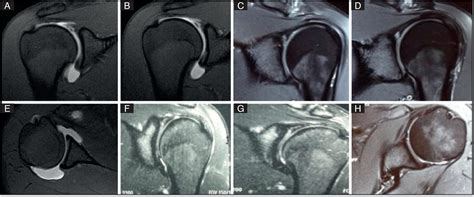

SLAP tears are classified into four types based on their severity and location:

Type Description

Type I Fraying of the superior labrum without significant tearing.

Type II Separation of the labrum and biceps tendon from the glenoid (shoulder socket).

Type III Bucket-handle tear of the superior labrum, where the tear extends into the biceps tendon.

Type IV Bucket-handle tear that extends into the biceps tendon, with a displaced flap of tissue.

Radiologists use specific criteria to classify SLAP tears based on their appearance on MRI images. For example, a Type II SLAP tear may show detachment of the labrum and biceps tendon from the glenoid, while a Type IV tear may exhibit a displaced flap of tissue.